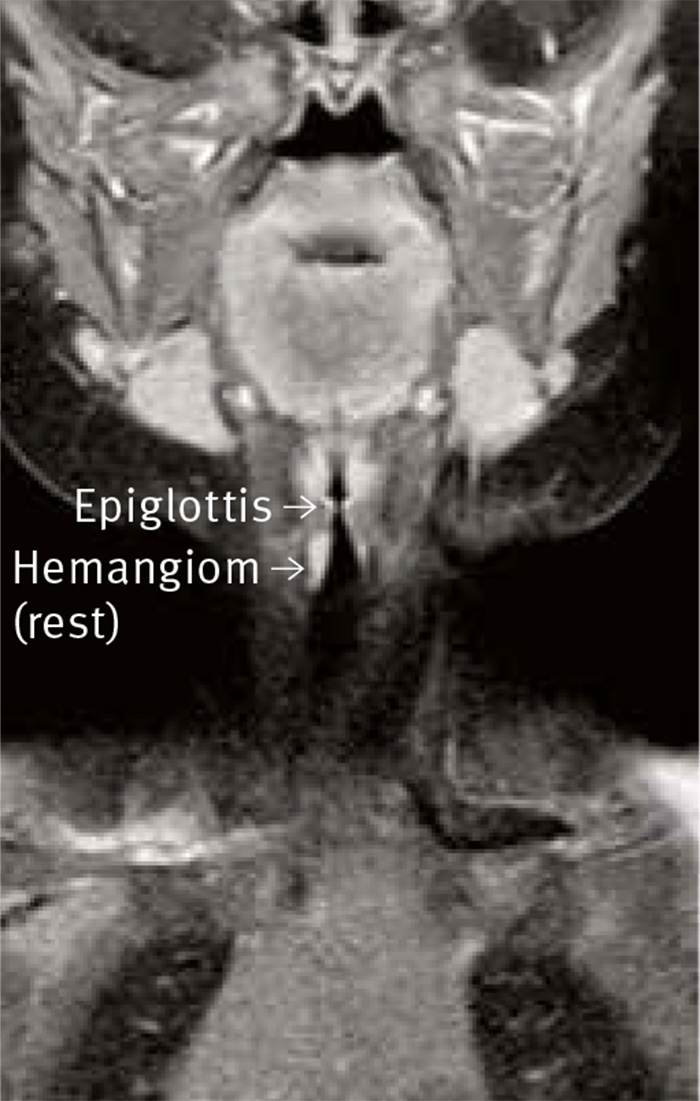

Under de följande månaderna mådde flickan bra. Vid kontroll 3 månader efter behandlingsstarten konstaterades att hon var helt symtomfri. Vid ultraljudsundersökning påvisades ingen påtaglig förändring av hemangiomet, men med förnyad MR-undersökning konstaterades att den kliniskt goda effekten av medicineringen också hade ett morfologiskt korrelat: I posterolaterala väggen av subglottiska trakea sågs en påtagligt förminskad förändring, en maximalt 2 mm djup, 5–6 mm bred och kranialt–kaudalt 7 mm lång bågformad, kontrastuppladdande rest (Figur 2).

Figur 2. Efter 4 månaders behandling sågs endast en rest av hem­angiomet.